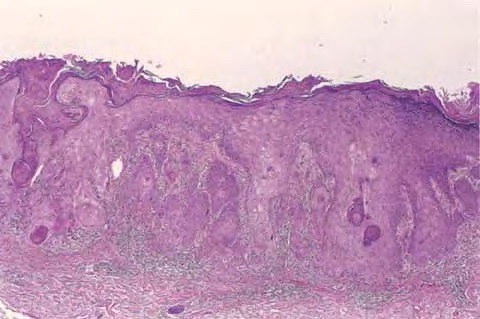

Squamous Cell Carcinoma = الكارسينوما شائكة الخلايا